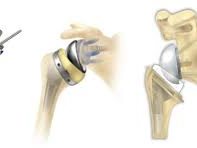

이런 경우에는 무릎 인공관절 치환술이 가장 효과적인 치료법으로 여겨지며, 수술 후에는 통증 완화 및 활동 능력 회복이 가능합니다.

일반적으로 무릎 인공관절 치환술은 한쪽 무릎 기준 300만 원에서 500만 원까지 발생할 수 있습니다. 수술 전 검사비, 입원비, 인공관절 재료비, 수술 후 재활치료까지 포함하면 금액은 더 늘어날 수 있습니다.

특히 고가의 인공관절 재료를 사용하는 경우에는 추가 비용이 발생하며, 병원의 등급 및 지역에 따라서도 수술비 차이가 큽니다. 이러한 비용은 저소득층에게 매우 부담스러울 수밖에 없습니다.